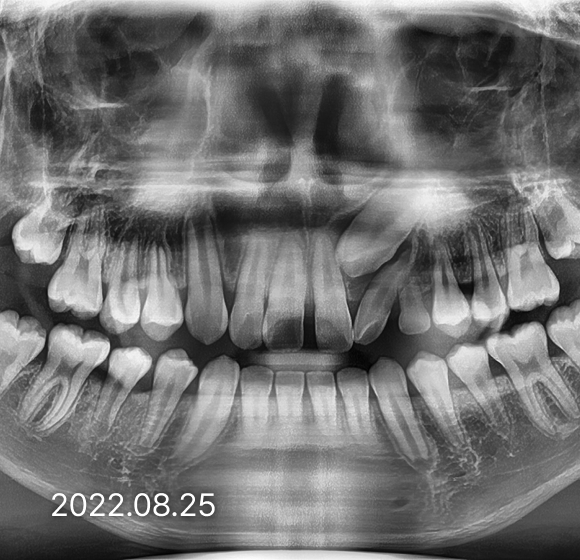

BEFORE / AFTER

전후 변화로 보는 치료사례

본 사진은 진심을담은치과교정과 치과의원에서

치료한 환자의 동일 인물 전·후 사진입니다.

개인의 구강 상태 및 관리 방법에 따라 통증 및 잇몸 염증,

턱관절 불편감 등의 부작용이 발생할 수 있습니다.

치료 전 치료 후

덧니, 삐뚤한 치열

돌출입

반대교합(비수술)

성장기 교정

과개교합

개방교합

치열공간, 벌어진 앞니

매복치아

악교정 수술 교정

결손치

부분교정

인비절라인